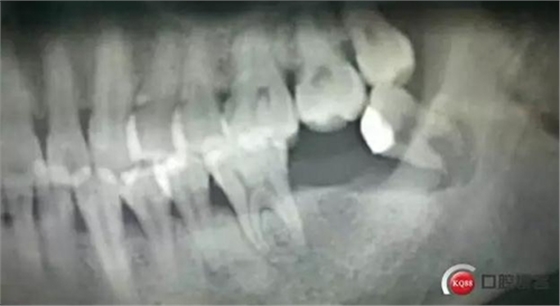

輔助檢查:曲面體層片示:38根尖區(qū)見一類圓形透射影,周緣可見明顯白色骨質(zhì)線。

確定診斷:38近中阻生 根尖囊腫 繼發(fā)感染